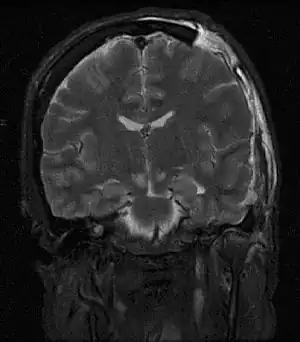

- Tomografia computadorizada (TC) ou uma ressonância magnética (MRI) do seu cérebro;